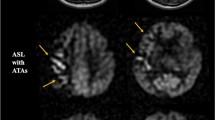

There were two types of hyperperfusion observed in this study. The first type is a significant perfusion signal increase in the surgery side that the absolute CBF value exceeds the value of the contralateral side (a representative case in Fig. 2). The second type is an evident low perfusion area in preoperative ASL, and after carotid surgery, the CBF increase filled up the low perfusion area, but the postoperative absolute CBF was comparable to the contralateral side (a representative case in Fig. 3).

Hyperperfusion type 2. A patient with right-side carotid stenosis. (a–c) Preoperative perfusion territory on territory-ASL. (d) Preoperative CBF of ASL reveals reduced CBF on the right watershed area, and intravascular high signal was seen on low perfusion area (arrow), indicating long ATT. e Postoperative CBF of ASL reveals regional CBF increase > 100%, but the mean perfusion signal on the right hemisphere is only a little higher than that of the contralateral side

CHS case 1. (a) Preoperative CTA indicates right ICA occlusion and severe stenosis of the left ICA. (b) Preoperative ASL reveals regional reduced CBF and higher signal heterogeneity on the right hemisphere. (c–e) Preoperative territory-ASL shows no perfusion of the right ICA and collateral flow from the left ICA and posterior circulation. Patient underwent left-side CAS and presented with seizure on the 7th postoperative day. (f) CT scan reveals intracranial hemorrhage on the left side. (g) Susceptibility-weighted imaging (2 months after surgery) reveals hypointensity in the sulci of the left hemisphere

CHS case 2. (a) Preoperative MRA reveals right A1 missing. (b–d) Preoperative perfusion territories showed by territory-ASL. The patient complained headache and soon developed into light coma. (e) Emergency CT demonstrated diffused edema of the left hemisphere. (f–h) Postoperative perfusion territories revealed by territory-ASL (3 months after surgery), no identifiable change compared with preoperative territory-ASL